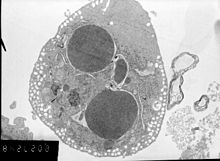

In order to perform analysis of apoptotic versus necrotic (necroptotic) cells, one can do analysis of morphology by label-free live cell imaging, time-lapse microscopy, flow fluorocytometry, and transmission electron microscopy. There are also various biochemical techniques for analysis of cell surface markers (phosphatidylserine exposure versus cell permeability by flow cytometry), cellular markers such as DNA fragmentation[70] (flow cytometry),[71] caspase activation, Bid cleavage, and cytochrome c release (Western blotting). It is important to know how primary and secondary necrotic cells can be distinguished by analysis of supernatant for caspases, HMGB1, and release of cytokeratin 18. However, no distinct surface or biochemical markers of necrotic cell death have been identified yet, and only negative markers are available. These include absence of apoptotic markers (caspase activation, cytochrome c release, and oligonucleosomal DNA fragmentation) and differential kinetics of cell death markers (phosphatidylserine exposure and cell membrane permeabilization). A selection of techniques that can be used to distinguish apoptosis from necroptotic cells could be found in these references.[72][73][74][75]

Methods for distinguishing apoptotic from necrotic (necroptotic) cells